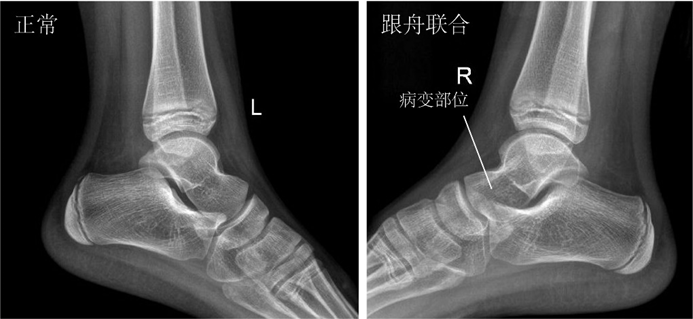

▶跟舟联合:是跟骨和舟骨之间的异常连接,发生率仅次于距跟联合。

▶跟舟联合——“食蚁兽鼻征”。

图6:跟舟联合X线片呈现“食蚁兽鼻征”